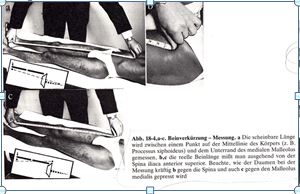

Der Mensch wird unbelastet auf dem Rücken liegend vermessen, ohne jede körperliche Ausweichhaltung zu berücksichtigen. Wie können so die spannungsbedingten Längenabweichungen, die sogenannten Beinlängen-Unterschiede Ursachen bezogen aufgezeigt werden?

1.1 Wie kann ein entlasteter Körper, ohne die Ausweichhaltungen zu berücksichtigen, eine reproduzierbare Längenabweichung gemessen werden? Wie verhält sich der Körper unter Belastung? | 1. Würden Sie ihr Auto auch aufs Dach kehren um die Radspur einzustellen? Wie würde sich das Fahrzeug unter Belastung verhalten? |